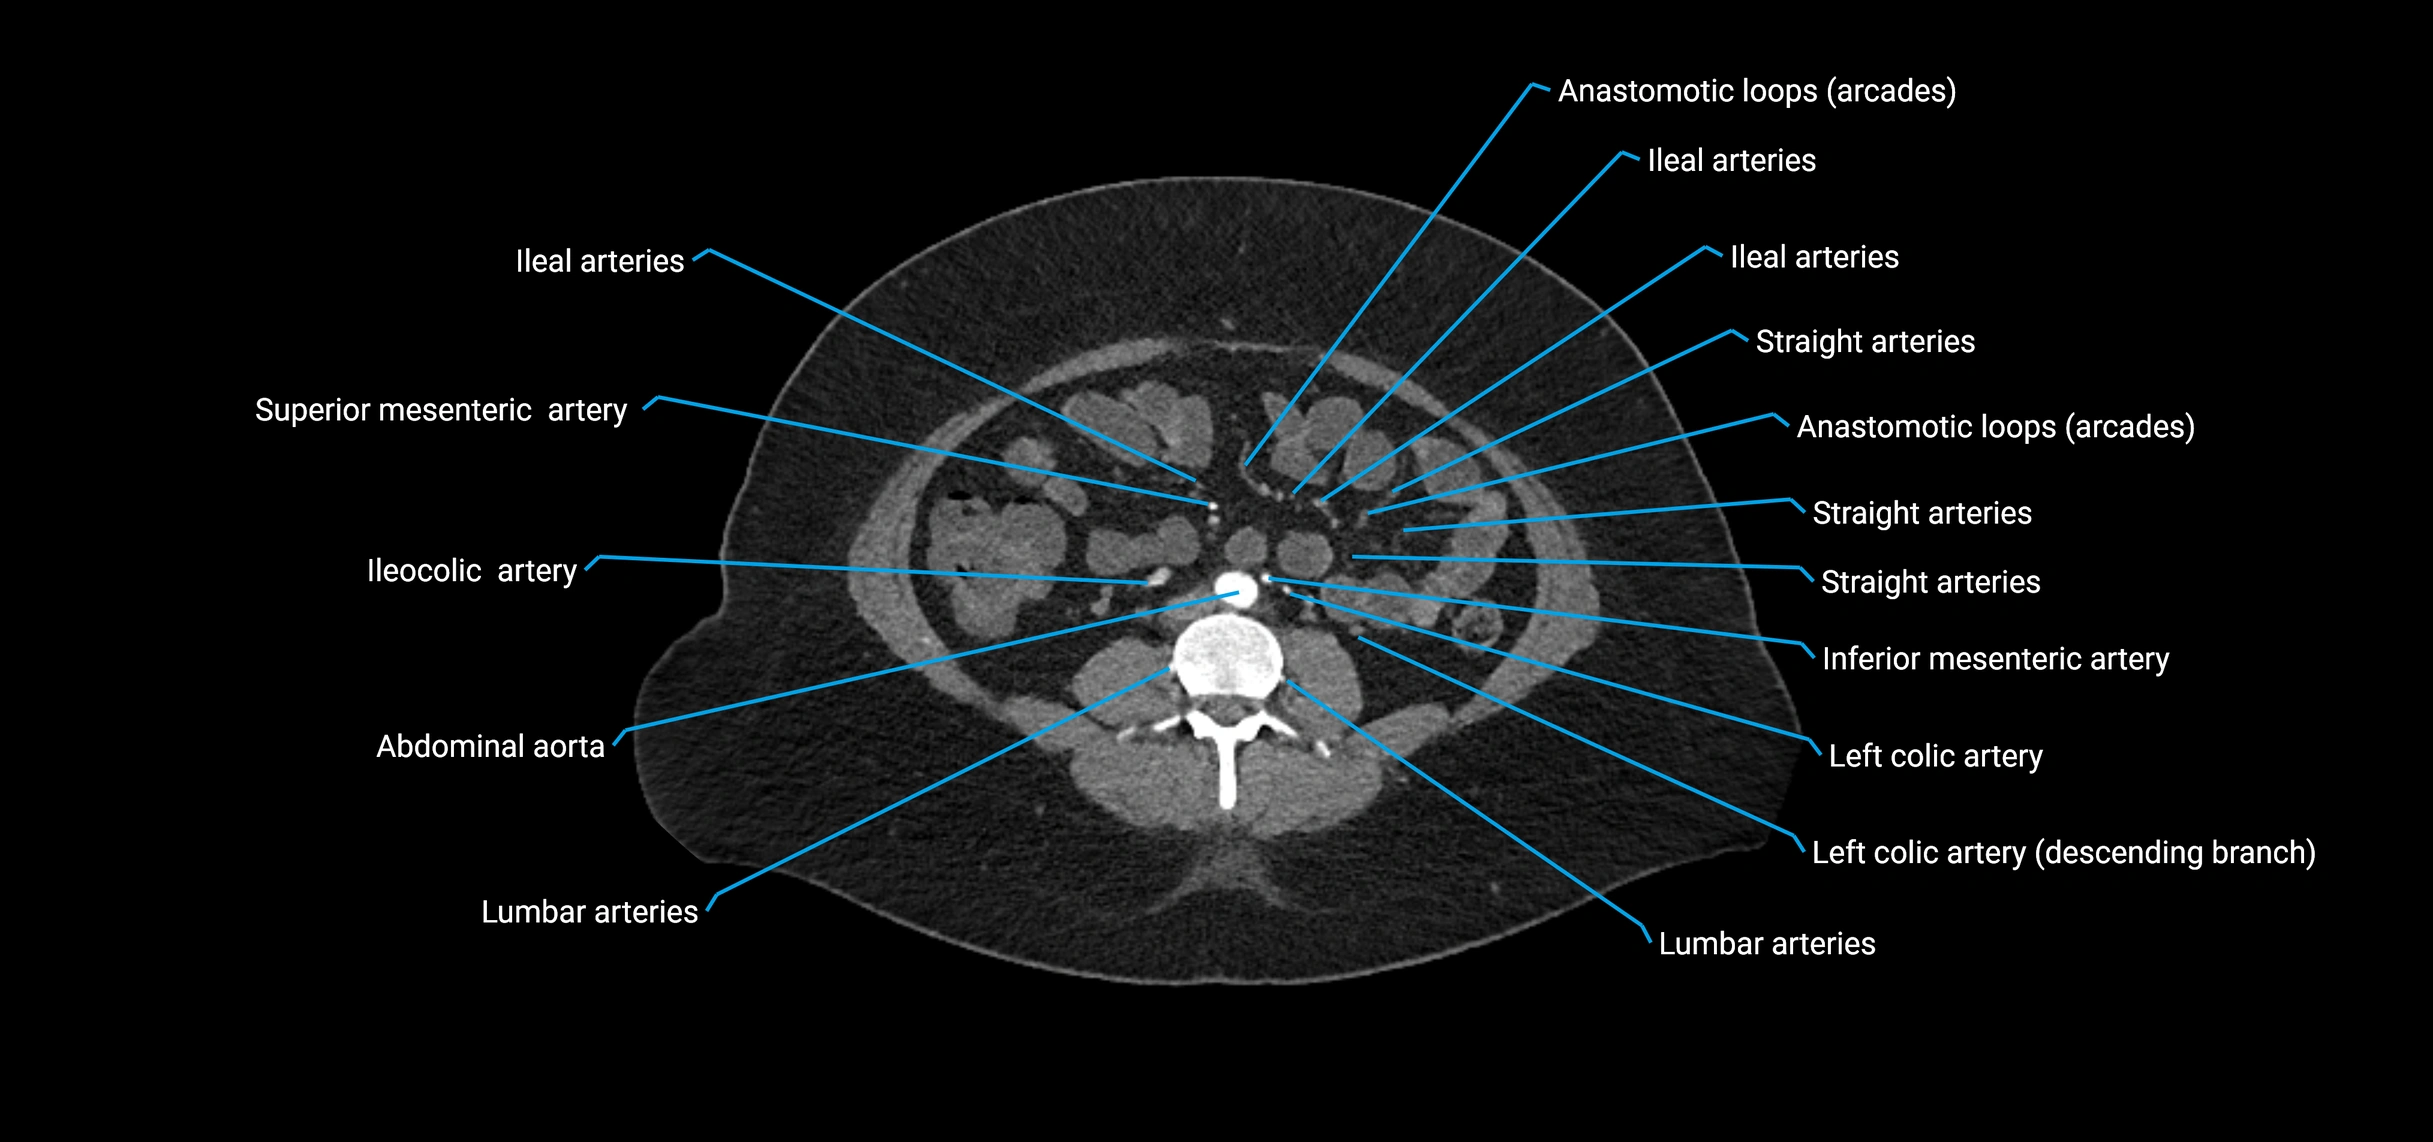

Contrast-enhanced CT (CTA):

• Gold standard for abdominal aortic imaging

• Provides excellent detail of lumen, wall, aneurysm, thrombus, and branch vessels

• Multiplanar and 3D reconstructions help in aneurysm measurement, stent graft planning, and dissection evaluation